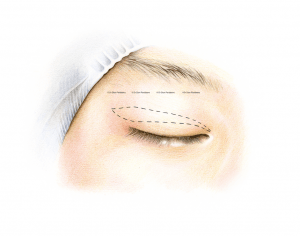

The most commonly performed eyelid surgery in people from East Asia is sometimes referred to as “double eyelid surgery”, and is a cosmetic surgical method that reconstructs the skin of the upper eyelid. Often oculoplastic surgeons also partially remove any skin surplus, which is a natural consequence of ageing. We oculoplastic surgeons can also create an eyelid crease – something that is naturally missing in people from East Asia (which is sometimes referred to as a “mono-lid”).

It is important that the doctor performing this procedure has special expertise in this area. Oculoplastic surgeons are ophthalmologists who specialize in eyelid surgery and who – like no other – understand the complex relationship between the eye and the eyelid. For example, an assessment of the different aspects of the eyelid such as eyelid height (the position of the lash line relative to the pupil), the amount of skin, the presence or absence of a so-called eyelid crease (the line above which the skin fold forms), the shape of the epicanthal fold, and the position and shape of the eyebrow should all be made preoperatively. It is also important to look for signs of dry (or wet) eyes, as this helps to prevent eye complaints after the procedure.

The operation of both upper eyelids takes about 45 minutes, but with the marking, explanation and postoperative cooling, the patient will be in the clinic for about 2 hours in total.